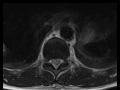

Epidural Hematoma with Spinal Cord Puncture Wound

48-year-old male stays post traumatic puncture injury to the mid-thoracic region. There is abnormal T2/STIR hyperintense signal within the central cord substance of the lower thoracic spinal cord at approximately the T10 vertebral level. Extending through the dorsal epidural space of the thoracic and upper lumbar spinal region, there is a T1, T2, and STIR hyperintense collection, compatible with an acute hematoma, partially effacing the thecal sac. The hematoma also contacts, displaces, and mildly deforms the upper to mid thoracic spinal cord with subtle central cord T2/STIR hyperintense signal compatible with edema. There are two smaller ventral epidural hematomas within the upper thoracic and upper lumbar spinal regions best demonstrated on the sagittal T1-weighted image. The axial images demonstrate the puncture would injury to the lower thoracic spinal cord substance with surrounding edema. There is also a dependent hematocrit level within the lumbar spinal canal on the axial T2 and sagittal STIR images. Spinal epidural hematomas are most common in the cervical or cervicothoracic region with extension over multiple levels. Epidural hematomas are most common over the posterior aspect of the thecal sac.